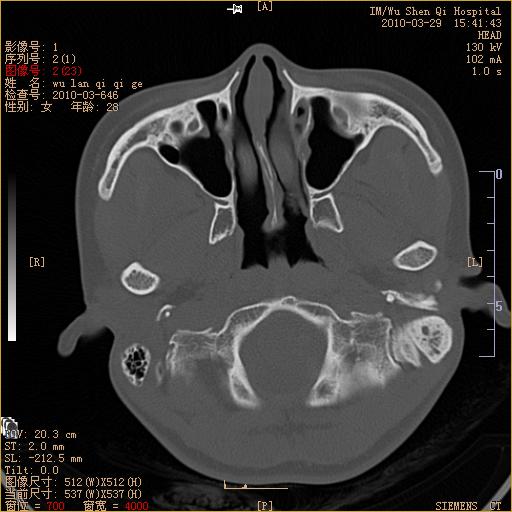

标题: CT25398:女,左耳流脓两年余,带有异物 [打印本页]

标题: CT25398:女,左耳流脓两年余,带有异物

左侧中耳乳突炎,不排除胆脂瘤形成。

左侧中耳乳突炎,胆脂瘤形成。

左侧中耳乳突炎,不排除胆脂瘤形成

1)左侧慢性中耳乳突炎并肉芽肿(或胆脂瘤)形成。2)考虑左侧颞骨慢性炎症伴骨质增生硬化,不排除骨纤。